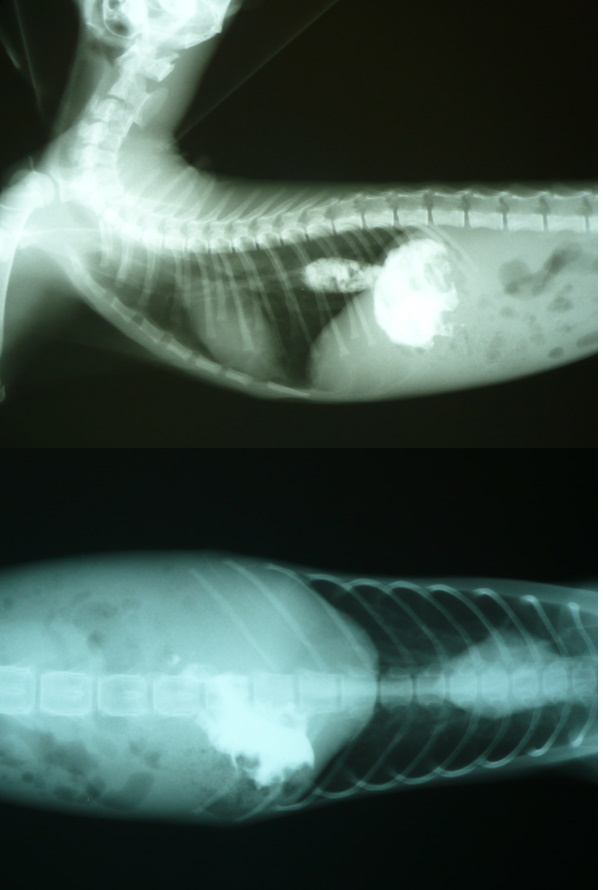

- 編號: 5111

主題: 營養不良路倒小黑貓 申請者姓名: 陳曉霏 花色: 申請日期: 2015-01-14 11:42:06 申請者部落格: 申請者臉書網址: 所在縣市/合作醫院: 台北市/長沁動物醫院 治療費用: 8520元 需求人數: 10人 已結案 (2015-02-24 12:15:35) 報名人員: Irene Hsu x2(已付款)、ruei(已付款)、林科(已付款)、Emily Yen(已付款)、Yang Hsu(已付款)、ERic YU(已付款)、ztsai(已付款)、徐阿悟(已付款)、徐阿悟、郭瑞希(已付款)、 候補人員: 動物病情說明: 是一個下雨的晚上

轉院後醫生原診斷孩子是因為

天生食道異常

所以任何進食的食物都吐出來

只能吃軟食或流質

但經過一段時間調養

食道卻神奇般沒事了 !!

研判可能孩子在外不會覓食

長期營養不良